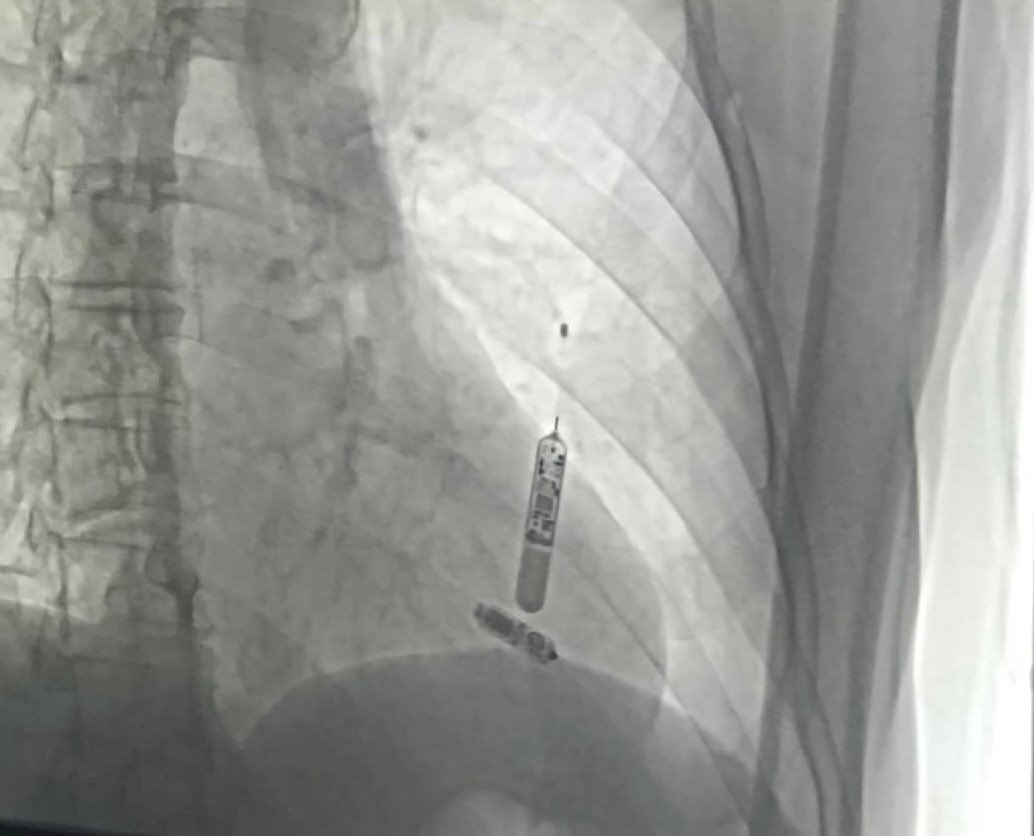

Right accessory pathway with a documented epicardial entrance. The ablation was successfully performed (endocardial approach!) by Professor Josep Brugada.@josep_brugada @carloskalil @celineboff @vaveck @mateuschrist @santacasapoa